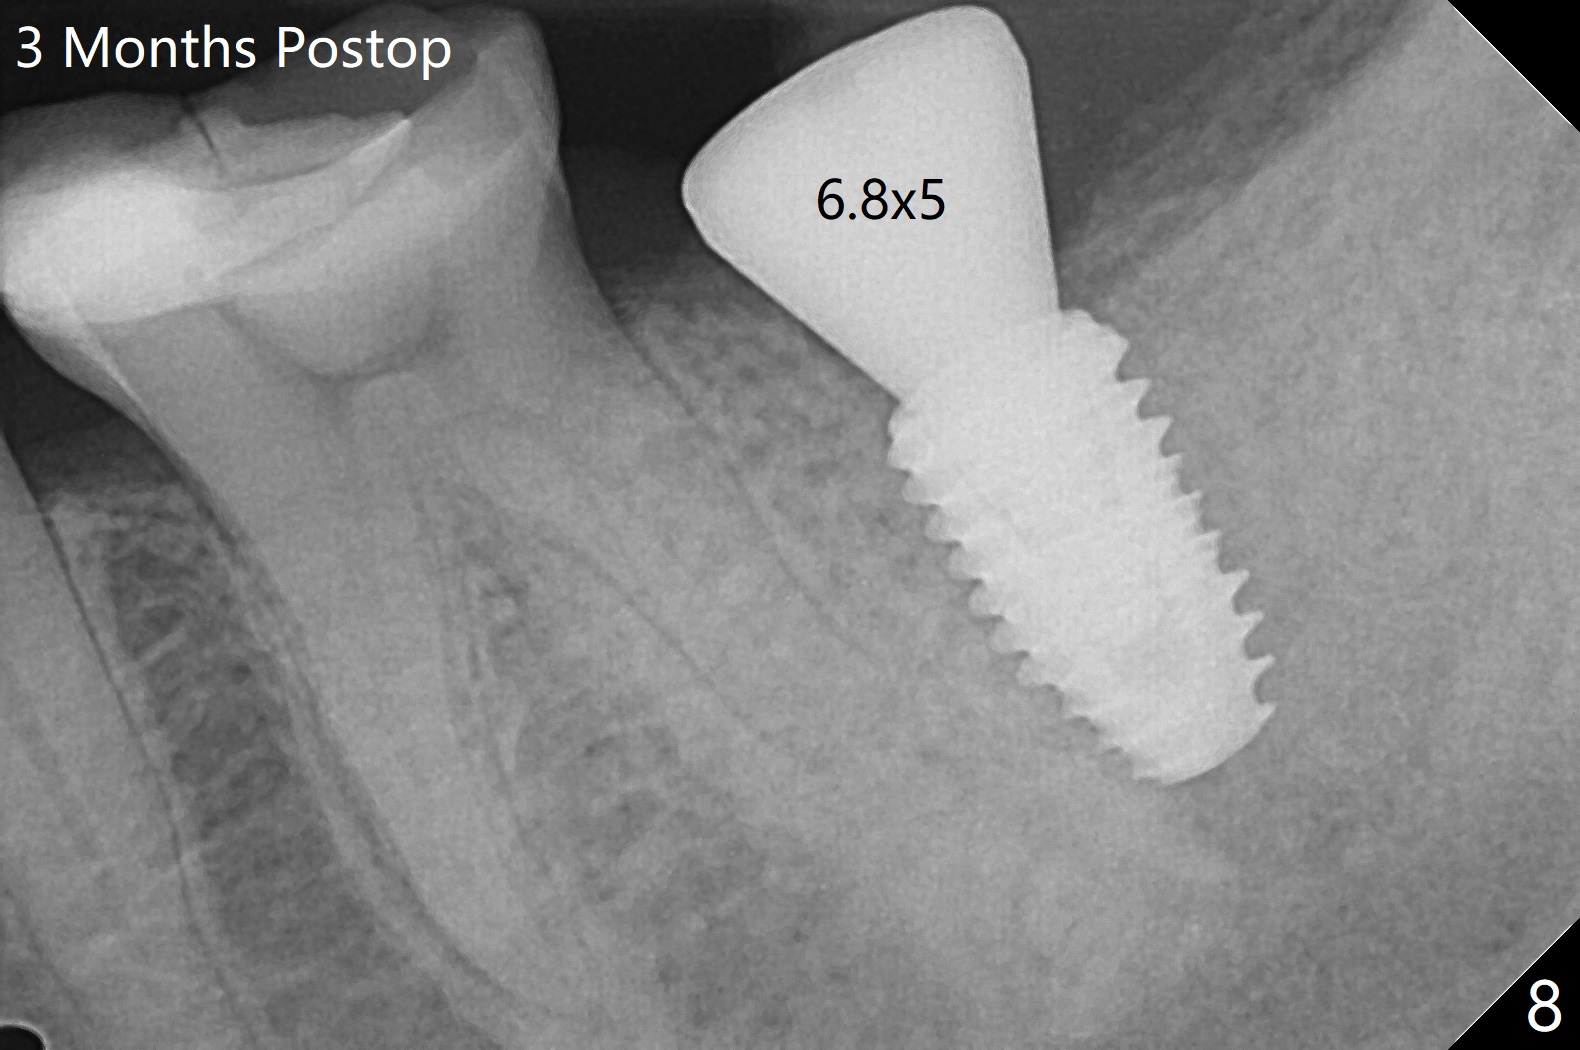

术前CT(图四):S:中隔。骨质密度低,拔牙时没植骨。植体容易进入近中牙槽窝。植牙设计:主要植入近中窝(图五),但是实际更近中。由于扭力低(骨质密度低),使用愈合螺帽,放置自体骨和胶原膜(C,GEM Cap),用牙周胶水固定(蓝色,图六)。胶原膜术后九天好像仍在原位(图七)。术后3个月牙槽嵴粘膜愈合正常,翻瓣后必须用钻头去除愈合螺帽冠方骨质,植体周围骨质密度增加(图八)。修复基台仿佛没有与牙槽嵴接触(图九)。调整基台高度后,取模。最后使用树脂水门汀。